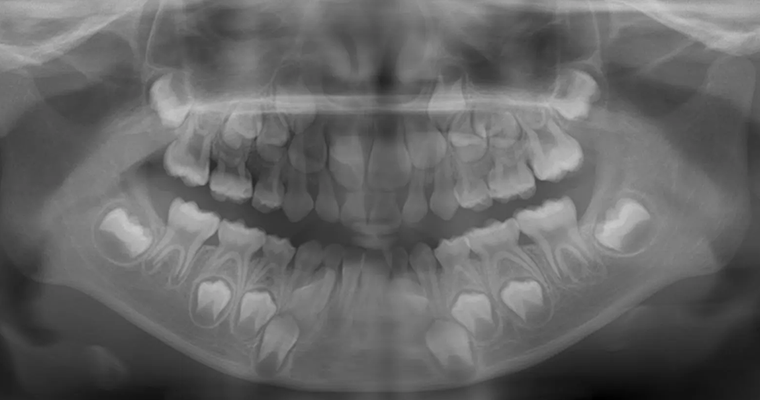

治療前 パノラマレントゲン

治療前 セファロレントゲン

| 主訴 | 歯並びが悪い 乳歯と永久歯が重なっている 歯がまっすぐはえてこない |

|---|---|

| 治療期間 | 6-7ヶ月 |

| 治療費 | 440,000円(税込) ※調整、器具、治療後にお渡しするEFLine(矯正後の後戻りを防ぐ器具)も全て込みでの金額となっております。 |

| 治療内容 | 拡大床矯正 EF Lineで筋機能療法 |